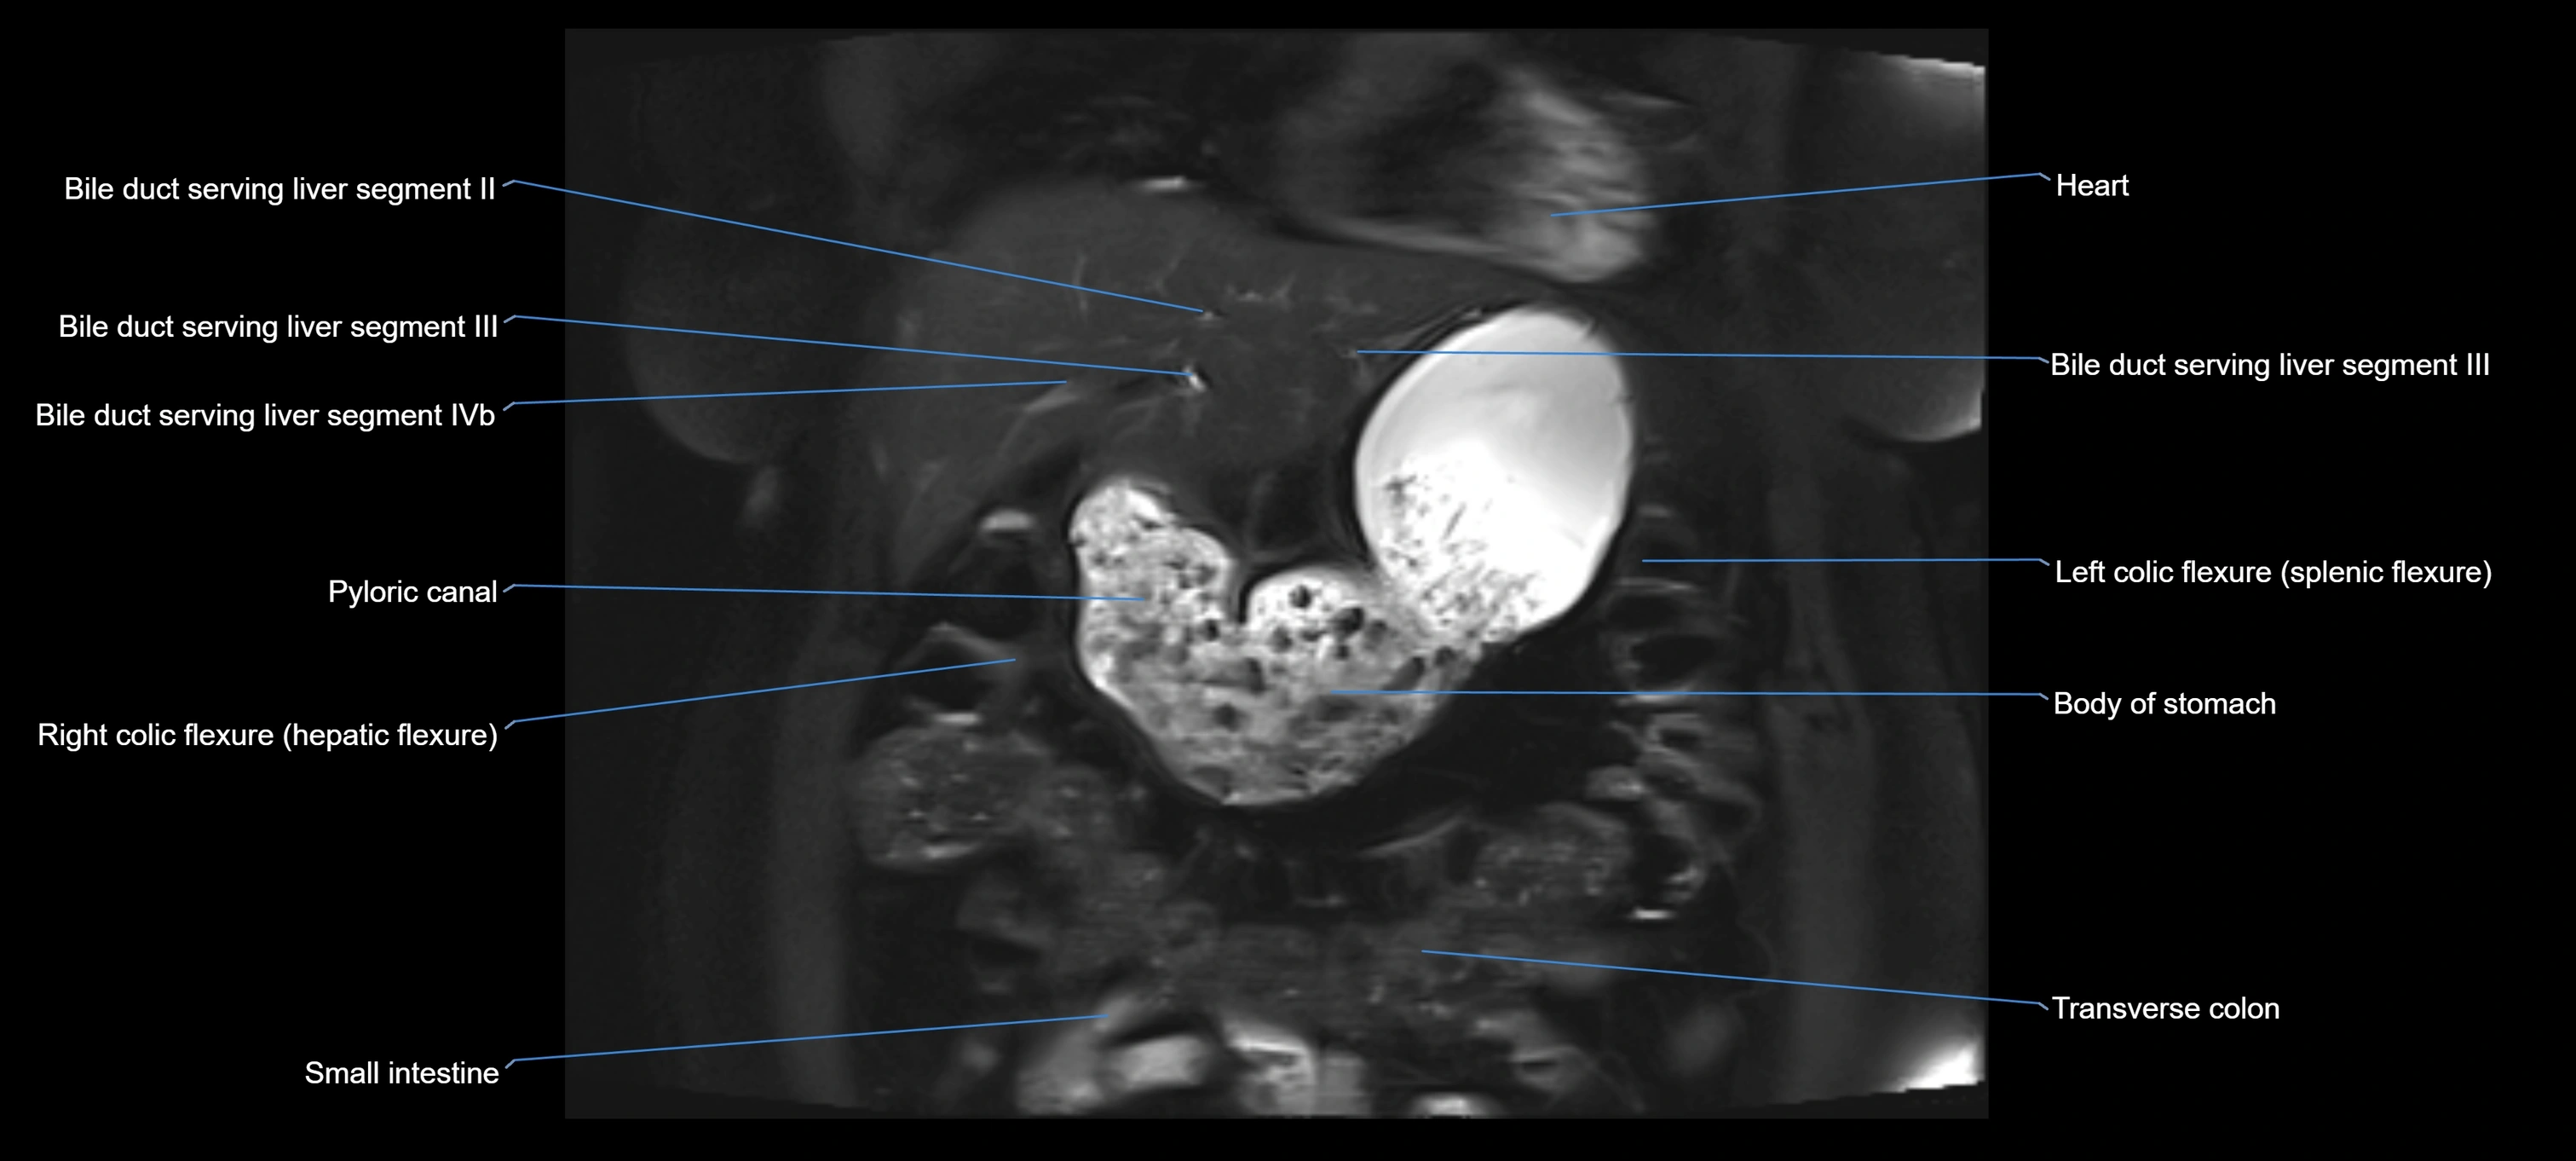

MRI Appearance

T1-weighted images:

• Not typically visualized unless dilated; appears as low signal tubular structure if seen

• Surrounding pancreatic parenchyma shows intermediate signal

T2-weighted images:

• Duct fluid appears bright

• Accessory duct seen as a fine high-signal tubular structure in pancreatic head

STIR (Short Tau Inversion Recovery):

• Duct fluid remains bright

• Surrounding fat suppressed, improving duct conspicuity

T1 Fat-Sat Post-Contrast:

• Normal duct does not enhance

• Surrounding inflammatory or neoplastic changes may enhance

T2 Fat-Saturated HASTE (single-shot):

• Accessory duct: bright, thin linear structure in pancreatic head

• Stones, strictures, or air bubbles appear as dark filling defects

• Excellent for rapid evaluation of duct patency

T2 TSE Fat-Saturated 3D (MRCP sequence):

• Duct visualized as a continuous bright tubular structure joining or parallel to the main pancreatic duct

• Allows 3D reconstruction of ductal anatomy and variants

• Excellent for diagnosis of pancreas divisum

Thick-slab T2 Fat-Saturated HASTE:

• Shows the accessory duct as part of the biliary–pancreatic system in a projectional image

• Highlights communication with main pancreatic duct and opening into the minor papilla

• Filling defects (stones, strictures) seen as dark spots within bright fluid

MRI image

image